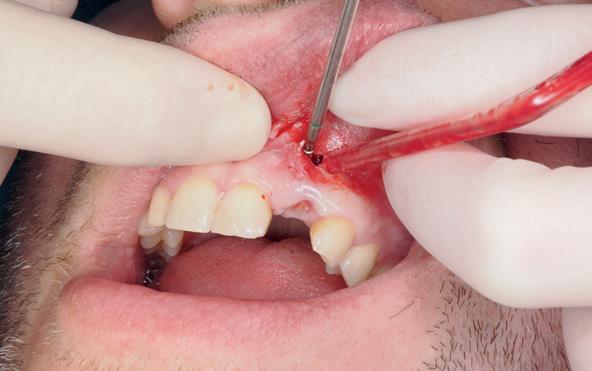

Implantologische behandelingen in het esthetische front vragen meer dan technische vaardigheid alleen. Ze vragen om overzicht, timing, vertrouwen en een team dat als vanzelf samenwerkt onder druk. Juist bij complexe casussen, waarin angst, infectie en hoge esthetische verwachtingen samenkomen, wordt zichtbaar hoe bepalend de rol van de tandartsassistent is.

Deze casus beschrijft een uitgebreide immediate implantaatbehandeling bij een patiënt die door meerdere collega’s werd geweigerd. Niet omdat de mogelijkheden ontbraken, maar omdat de complexiteit vroeg om een perfect afgestemde samenwerking. Het verhaal laat zien hoe de assistent in zo’n traject veel meer is dan een uitvoerende kracht of “mal”, maar een dynamische surgical guide die het proces mede stuurt, bewaakt en mogelijk maakt.De patiënt: wanneer alles samenkomt

Ze kwam binnen op een dinsdagochtend, iets voor achten. Een vrouw van begin zeventig, met een zachte stem en ogen die meer vertelden dan haar woorden. Ze vertelde dat ze een eigen B&B had en dat ze zich nauwelijks kon voorstellen gasten te ontvangen zonder tanden. Op dit moment kon ze echter nauwelijks lachen. “Het doet pijn… en het ruikt soms ook niet goed,” zei ze bijna verontschuldigend. Haar oude bovenbrug, die ze al meer dan twintig jaar droeg, was langzaam maar zeker ingestort. Er was sprake van cariës onder meerdere pijlers, pusafvloed,

chronische ontsteking en een brug die mobiel was en elke beet pijnlijk maakte. Ze had inmiddels meerdere tandartsen bezocht. Drie hadden haar geweigerd. Te complex. Te veel wensen. Te onvoorspelbaar.

De kern van haar vraag was eenvoudig en tegelijkertijd uitdagend: Is het mogelijk om mijn huidige brug te dupliceren en een nieuwe brug te vervaardigen met minder complicaties?

De basis van een complexe beslissing

Mijn behandelplan begint altijd met een uitgebreid klinisch onderzoek. Dat omvat een medische anamnese, intra- en extra-orale camerafoto’s en uitgebreid verwachtingsmanagement. In deze fase is mijn assistent vooral bezig met het zorgvuldig vastleggen van alle gegevens. Juist dat nauwkeurig documenteren zorgt voor rust in de behandelkamer. Minstens zo belangrijk is het luisteren naar de patiënt. Niet alleen naar de klachten, maar naar het

levensverhaal en de mens achter de brug. Begrijpen wat deze behandeling voor iemand betekent, is cruciaal voor het uiteindelijke succes.

Na het klinische onderzoek volgde het röntgenologisch traject. De CBCT liet precies zien wat we al vreesden: een front waarin het bot onregelmatig was, duidelijke radiolucenties rond de pijlers en een infectiegebied dat zich onder vrijwel de gehele brug had verspreid. Tegelijkertijd was er ook potentie. Net voldoende botstructuur om immediate implantaatplaatsing te overwegen, mits alles perfect gepland zou worden.